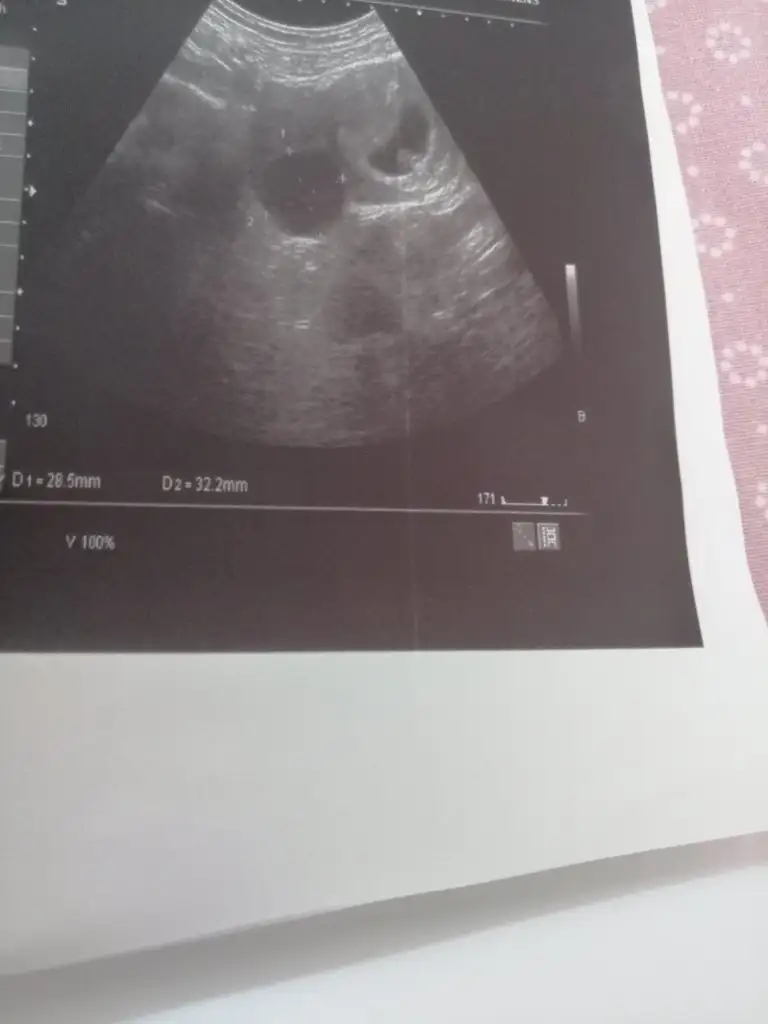

Bizim ufaklık için tahmininiz var mı acaba?

Çok net değil ama bu haftaki usg’miz bu şimdilik

11+1

Eki Görüntüle 2752990